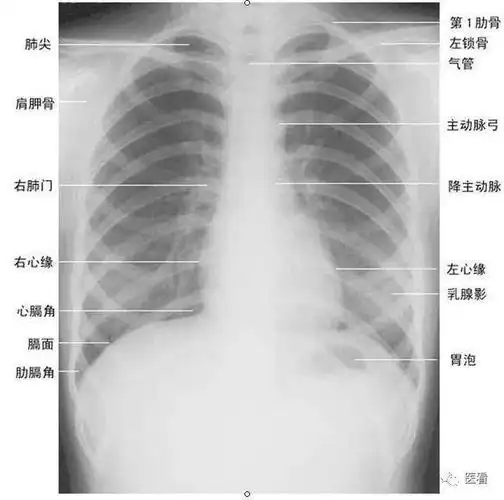

读完此文,终于会看儿童胸片了_传播

技能考试—读阅胸片基础

看胸片的秘诀终极版:你真的读懂了吗?